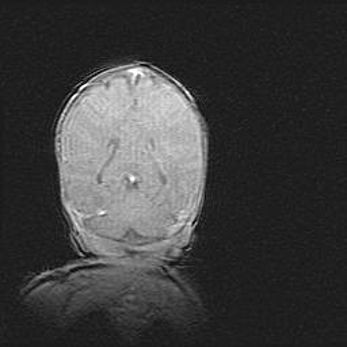

Наружная гидроцефалия с возможной атрофией височных областей.

Возраст: 28 дней

Вес: 3670 г

Пол: мужской

Окружность головы: 38 см

Срок гестации: 40 недель

Гидроцефалия головного мозга у новорожденных – это заболевание, которое характеризуется скоплением избыточного количества спинномозговой жидкости в желудочковой системе головного мозга в результате затруднения её перемещения от места выработки к месту поглощения в кровеносную систему или вследствие нарушения абсорбции. При открытой наружной форме гидроцефалии у новорожденных расширяются и переполняются субарахноидные пространства.

При нормотензивных  формах,  которые,  как  правило,  являются  следствием  перенесенных ишемических  повреждений  паренхимы  мозга,  возможно  сочетание микроцефалии  с нормотензивной гидроцефалией. В основе данных изменений лежит атрофия больших полушарий с преимущественной  локализацией  в  лобно-височных  областях.